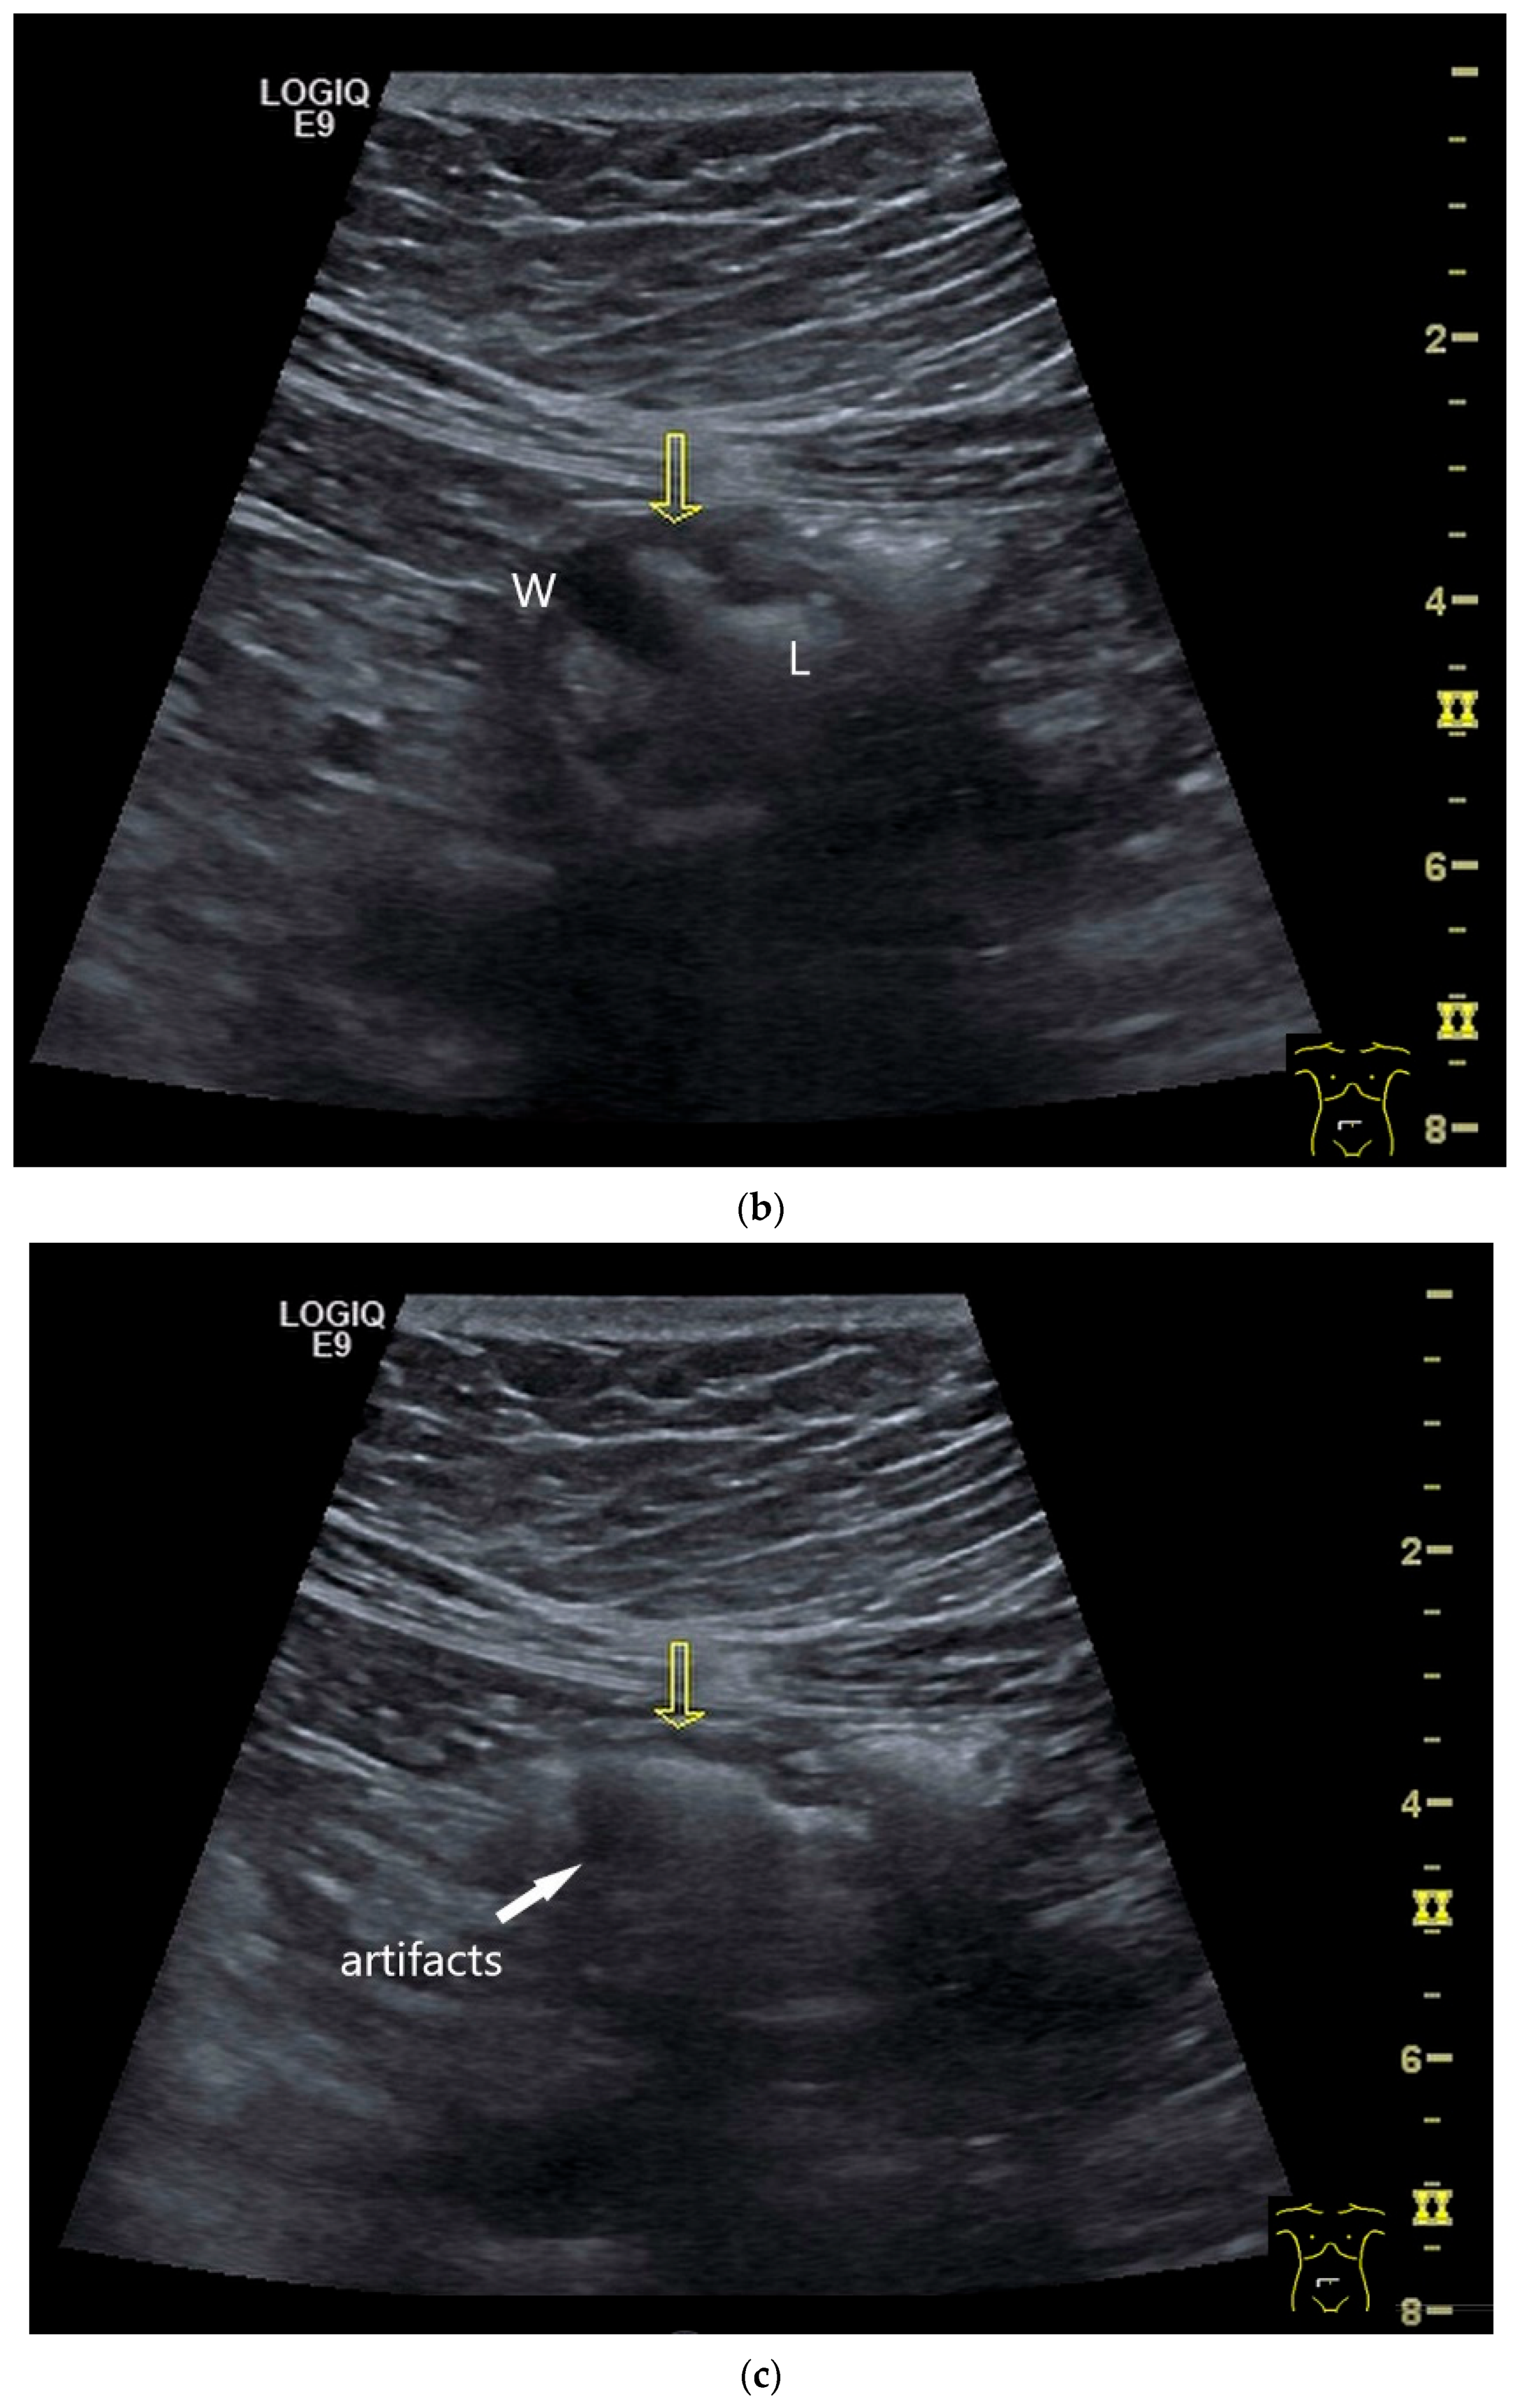

Imaging: Tumors in the jejunum and ileum are usually circular ring-shaped and lumen-stenosing. In the duodenum, about one third have a polypoid component, but a proportion of cases show plaque-like growth [70]. On US, the adenocarcinoma presents as hypoechoic wall thickening with lumen narrowing. The infiltrative wall process may show further tongue-shaped hypoechoic infiltrations into the surrounding tissue. In the case of lymph node involvement, the mesenteric lymph nodes at the level of the tumor may be enlarged and/or morphologically conspicuous [71,72] (Figure 5 and Figure 6).

Figure 5.

Adenocarcinoma in the duodenum. Significant hypoechoic wall thickening (between the markers) with narrowed lumen reflexes (a). The tumor has a slightly polycyclic border on the outside (a,b). Several tumor-suspicious, round, hypoechoic lymph nodes (L) are visible in the paraduodenal region (b).

Figure 6.

Jejunal Adenocarcinoma. Segmental hypoechoic wall thickening (arrows) in the jejunum discovered during anemia diagnostics. Kerckring folds are faintly visible (KF) (a). Adjacent to this is a large round hypoechoic lymph node (L). The surrounding area shows hyperechoic changes (b).